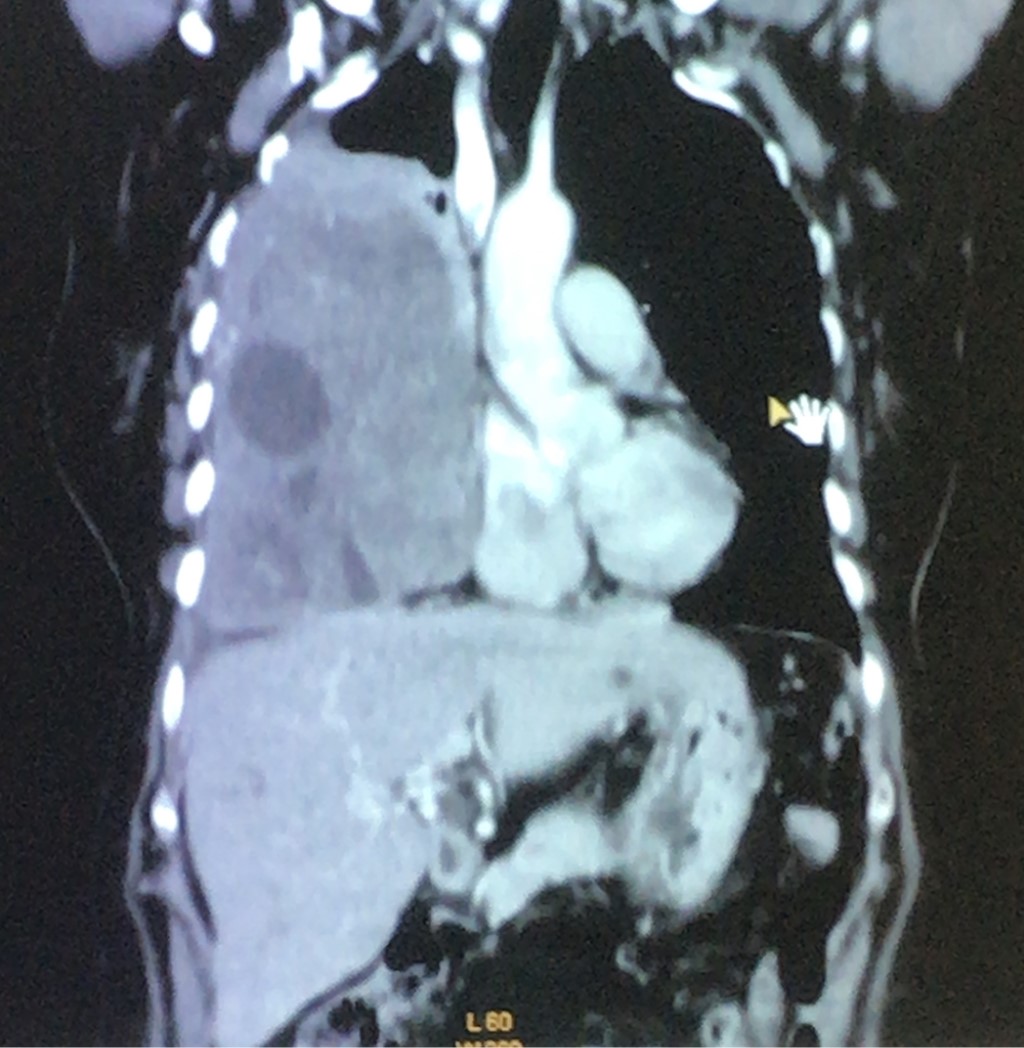

Se efectúa biopsia por punción. El informe de anatomía patológica es: tumor fusocelular, DC 34 negativo, ASMA positivo, S 100 negativo, NSE negativo, Ki67 2% que sugiere como diagnóstico leiomiosarcoma de bajo grado. Se solicita resonancia magnética para visualizar la presencia de infiltración, principalmente de grandes vasos (Figura 2), y estudios para enfermedad a distancia, sin encontrar imágenes compatibles (Figura 3) con metástasis. Se decide, junto con la paciente, familiares y Servicio de Oncología, la conducta quirúrgica para lograr extirpación completa o la mayor resección posible.

Figura 3